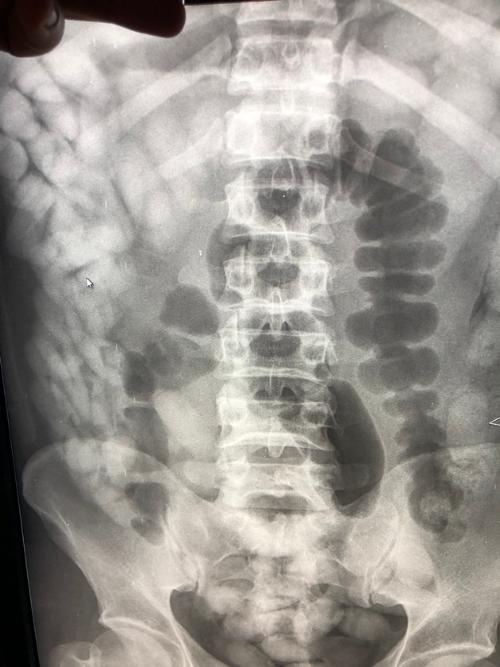

Die Beamten führten daraufhin einen Drogenwischtest durch, der Kokain anzeigte. Da weder am Körper noch im Gepäck des Reisenden Kokain gefunden wurde, musste der Mann im Krankenhaus geröntgt werden.

„Das Röntgenbild bestätigte den Verdacht der Zöllner. Im Laufe des Tages kamen 97 Behältnisse mit Kokain zum Vorschein, die über den natürlichen Weg ausgeschieden wurden“, so Marie Müller, Pressesprecherin des Hauptzollamts München.